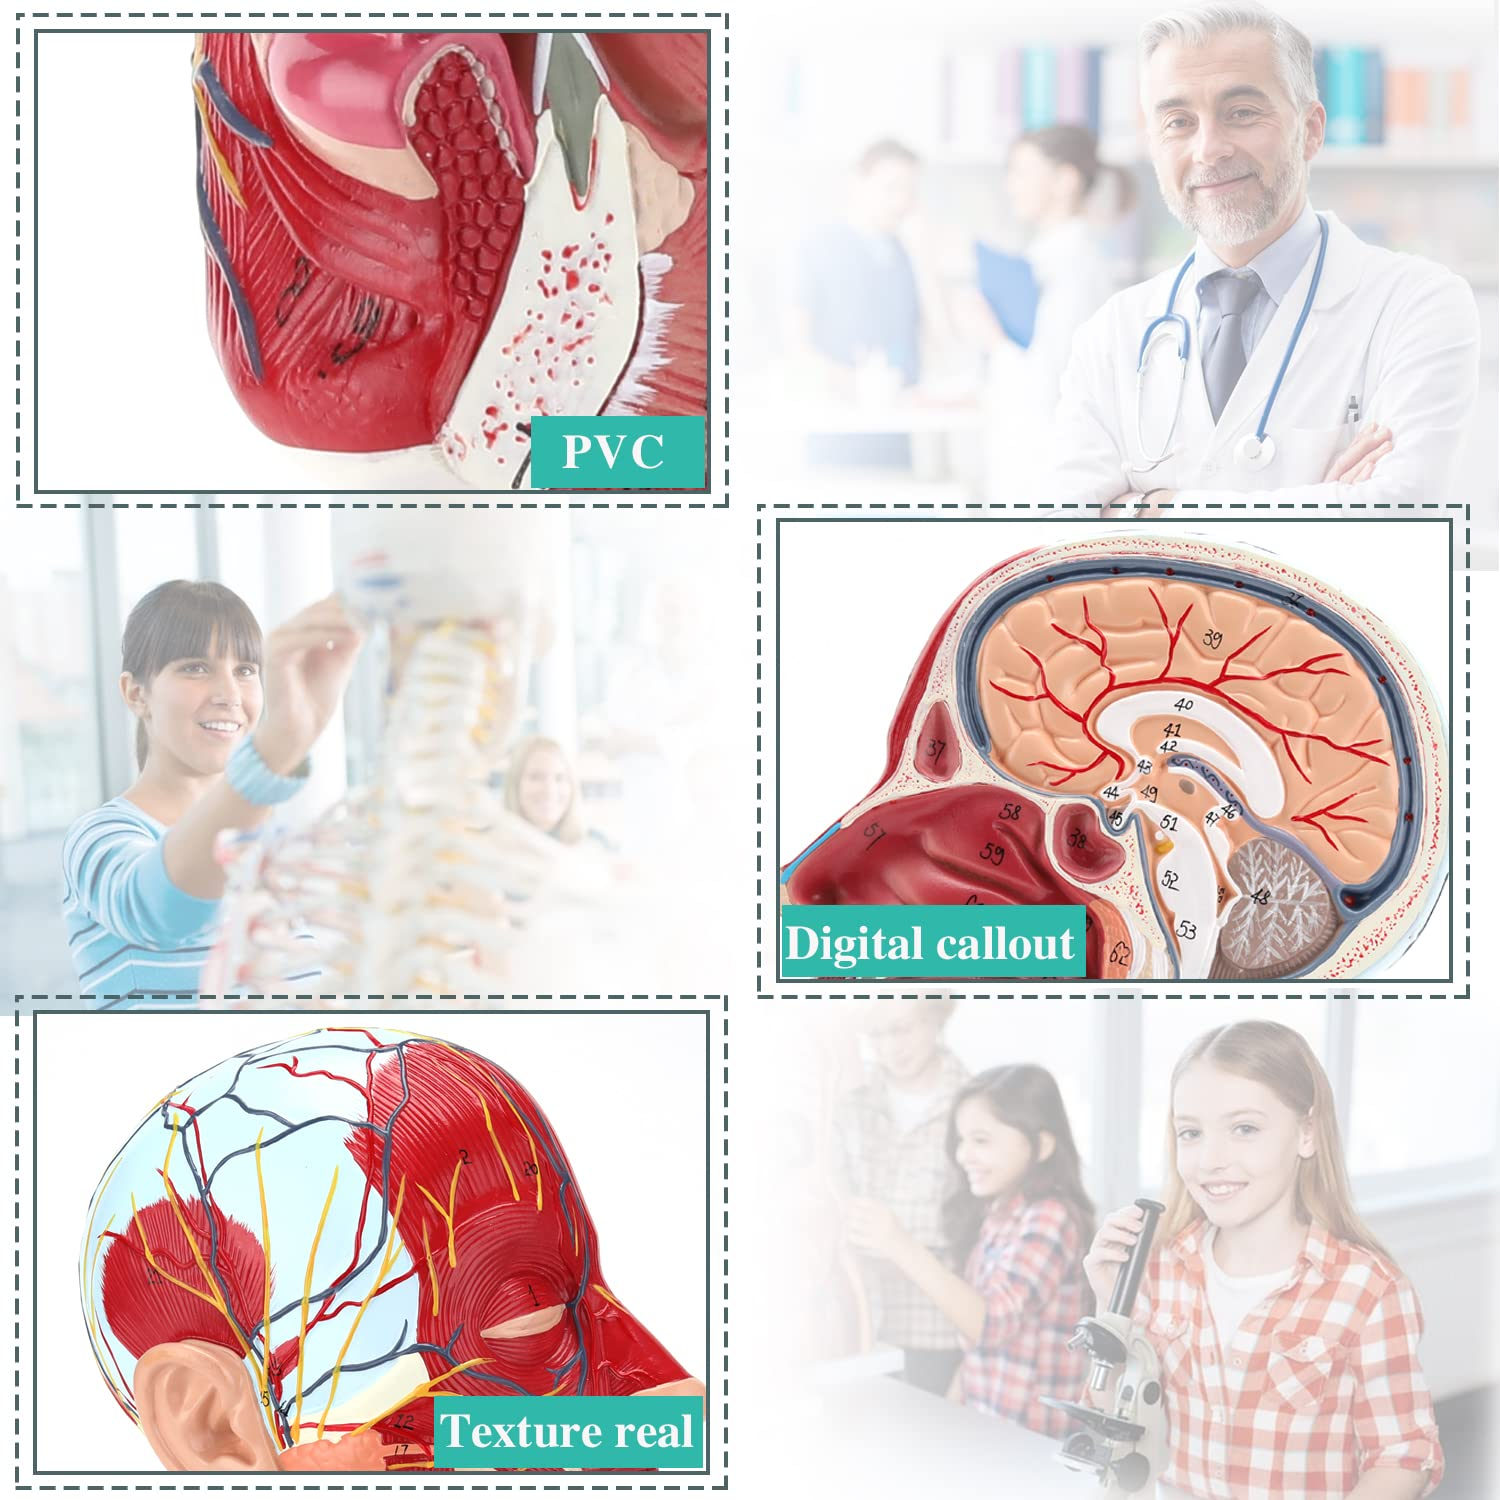

| Material | PVC |

【Modelo de anatomia cerebral de alta qualidade, feita de material não tóxico de PVC ambientalmente amigável, fácil de limpar. Os modelos de anatomia são pintados à mão e montados com a máxima atenção aos detalhes.

【Modelo superficial do músculo neurovascular】 Números altamente detalhados, marcados e destacáveis, aprofundar o entendimento dos músculos superficiais, vasos, nervos e as estruturas internas da cabeça e pescoço. Artéria vermelha, azul-veia, nervo amarelo.